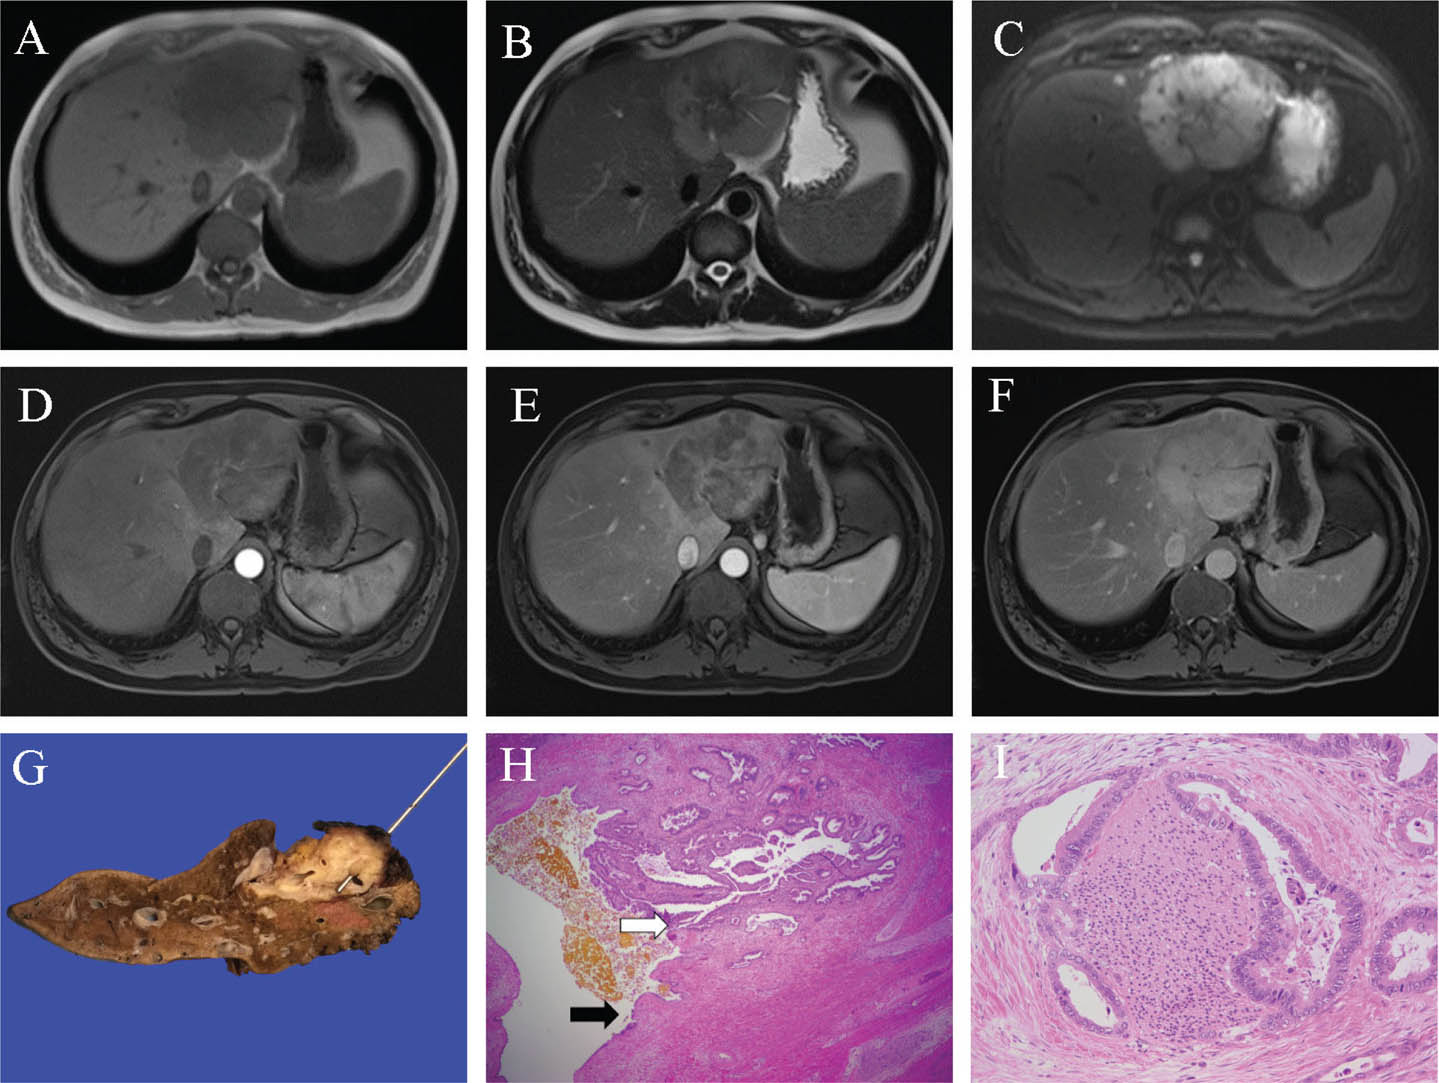

Fig 3

Figure 3. Representative images of hepatocellular carcinoma. A. Transverse ultrasound image of the liver demonstrates a new hyperechoic lesion in a cirrhotic liver, highly suspicious for HCC. B and C. The lesion in segment 6 shows signal loss on the opposed phase T1 weighted image (C) compared to the in-phase T1 weighted image (B) denoting microscopic fat content. D. The lesion shows heterogeneous high signal on the T2 weighted image. E and F. Following gadolinium administration, the lesion shows heterogeneous arterial enhancement (E) and portal phase wash-out (F). G. A representative slice of liver from an explant of a separate patient shows a soft variegated lesion grossly (white arrow), ranging from green to red-brown, embedded in a firm cirrhotic liver parenchyma. H and I. There is a loss of normal hepatic architecture with trabecular and pseudoglandular growth patterns (H) of malignant cells with enlarged vesicular nuclei and eosinophilic cytoplasm (I). Slides are stained with Hematoxylin and Eosin. Total image magnification: H - 25X; I - 400X.

Grossly, HCC is soft with a variegated appearance ranging from green to light tan depending on bile and fat content respectively, and foci of hemorrhage or necrosis. Tumors may have a capsule of fibrotic and inflamed tissue and can be seen invading large vascular structures. Fibrolamellar and scirrhous subtypes may appear firmer and more fibrotic compared to conventional HCCs, and these features may mimic the central scar of FNH or even cholangiocarcinoma. Fibrolamellar carcinoma is a distinct lesion affecting younger adults without pre-existing cirrhosis or elevated serum AFP. It is typically a large mass with calcification, hemorrhage, or necrosis, can mimic FNH with a central scar, commonly metastasizes to lymph nodes and distant sites, and shows a DNAJB1-PRKACA fusion transcript (1718).

Microscopically, HCC shows variable degrees of cytological and architectural atypia with thickened hepatic plates and disruption/loss of the reticulin framework. Hepatocellular differentiation is often apparent on hematoxylin and eosin (H&E); however, IHC stains (Hep Par-1 and Arginase-1) are sometimes necessary for poorly differentiated tumors to establish hepatocellular origin. Furthermore, careful examination of reticulin stain and identification of abnormal expression of Glypican-3 IHC may be required in well-differentiated tumors to establish a diagnosis of carcinoma. Increased arterial blood flow leads to sinusoidal capillarization, which can be demonstrated by CD34 IHC. There are four predominant growth patterns including trabecular (70%), solid (20%), pseudoglandular (10%), and macrotrabecular with cell plates greater than ten cells in thickness (1%), although mixed patterns are common (19). Approximately 35% of HCCs show distinct clinicopathologic subtypes, including steatohepatitic (most commonly in patients with underlying fatty liver disease), clear cell (cytoplasmic clearing secondary to glycogen accumulation), scirrhous (fibrosis in the majority of the tumor, separate small nests of tumor cells in thin trabeculae), and fibrolamellar (large polygonal hepatocytes with abundant cytoplasm and prominent nucleoli, pale bodies, thick collagenous bands in parallel orientations, and non-cirrhotic background liver) (20). Combined hepatocellular cholangiocarcinoma is a rare diagnosis with convincing HCC and cholangiocarcinoma morphologies present within the same tumor.

Across imaging modalities, differentiation of small HCCs from regenerative or dysplastic nodules can be challenging in the setting of cirrhosis. Smaller lesions are typically homogenous, with larger lesions demonstrating variable heterogeneity secondary to the variable presence of fat, fibrosis, necrosis, hemorrhage, and calcification. The American College of Radiology (ACR) Liver Imaging and Reporting Data System (LI-RADS) version 2018 provides a validated set of standardized diagnostic criteria for HCC based on CT/MRI. It has become integrated into the American Association for the Study of Liver Diseases (AASLD) clinical practice guidelines (2223). LI-RADS provides uniformity and improved accuracy in diagnostic reporting, including consistency in imaging work-up options and follow-up time intervals.

On ultrasound, small HCCs are usually hypoechoic, with larger lesions demonstrating variable echogenicity and heterogeneity. A thin hypoechoic pseudocapsule may be seen. Doppler may demonstrate vascularity and arteriovenous shunting. Increased arterialisation and progressive loss of the portal-venous vascular contribution results in a characteristic pattern on contrast-enhanced ultrasound, CT, and MRI of late arterial hyperenhancement with decreased enhancement relative to liver parenchyma (wash-out) on delayed phases, variably present on the portal-venous phase (24). Unenhanced CT has limited sensitivity for HCC, typically hypoattenuating if detected.

Contrast-enhanced MRI (extracellular or hepatobiliary gadolinium agents) shows significantly higher sensitivity for HCC than contrast-enhanced CT in the setting of cirrhosis (82% vs. 66%) with similar specificities (91% vs. 92%) (25). Approximately 20% of HCCs arise in non-cirrhotic livers, with contrast-enhanced MRI also demonstrating high sensitivity (91%) and specificity (75–98%) (26). HCC is usually T1WI isointense to hypointense, and T2WI heterogeneously intermediate to high signal. Late arterial hyperenhancement is typically homogenous for smaller lesions and more heterogeneous for larger lesions. Portal-venous phase wash-out is variable depending on size, with smaller lesions typically retaining a degree of perceptible enhancement and larger lesions demonstrating greater wash-out compared to the adjacent liver. With delayed phases, lesions typically demonstrate wash-out with residual enhancement in the pseudocapsule, if present. A recognized pitfall is that small (<2 cm) early HCCs may show a lack of delayed phase washout, and close imaging follow up of these lesions in the cirrhotic liver is required. DWI shows diffusion restriction in areas of high cellularity and cell membrane density (for example, malignancy) (27). DWI increases the sensitivity of conventional extracellular contrast-enhanced MRI, especially for small (<2 cm) HCCs (28). Sensitivity for HCC with gadoxetic acid contrast-enhanced MRI is improved (95.2%) when including wash-out criteria for the hepatobiliary phase (29).